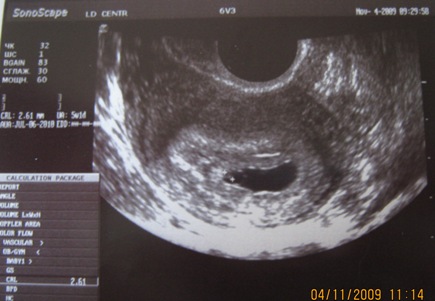

Наше первое УЗИ)))И моя крошка!!!!

Результаты: УЗИ, КТГ, доплера, скринингаВот моя крошка...все у нас хорошо, растем!!! мы малюсенькие и сердечко не слышно еще!!! а так хочелось услышать)))

нам 5недель и 1 день.

Яйцо ф-19*22 мм

КТР-2,6 мм,( что это такое КТР?)

желт.мешочек -5 мм.

Поздравляю с знакомством! Два дня-ерунда. Когда замеры делали могло появиться расхождение,да и вообще-имей ввиду,что аппарат оценивает размеры малыша,и только исходя из них ставит срок. А размеры. Понятие относительное. Тут играет роль генетика,некоторые малыши скачками растут,ну,и когда узи делают,с размерами могут немного ошибиться тоже. А ктр-копчиково-теменной размер. То есть твоя кроха от темени до попки 2,6 мм!